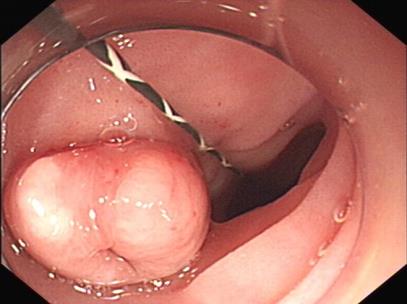

• 内镜下套扎手术和外科痔切除术治疗内痔的临床价值比较

2025, 31(11):40-46. DOI: 10.12235/E20250460

摘要 (117) HTML (45) PDF 749.91 K (78) 评论 (0) 收藏

摘要:目的 比较内镜下套扎手术与外科痔切除术对内痔的治疗价值。方法 选择2023年2月-2025年4月该院收治的340例内痔患者,根据治疗方法分为两组,行外科痔切除术的160例患者为对照组,行内镜下套扎手术的180例患者为观察组,比较两组患者手术相关指标,评估术后肛门疼痛情况,检测手术前后血清炎症因子、肛门功能、肛肠动力学指标和肛门狭窄程度,统计并发症情况。结果 观察组手术时间明显短于对照组,术中出血量明显少于对照组,治疗费用明显低于对照组,差异均有统计学意义(P < 0.05)。术后1和7 d,观察组疼痛视觉模拟评分法(VAS)评分明显低于对照组,差异有统计学意义(P < 0.05);术后1个月,观察组血清炎症因子水平明显低于对照组,差异有统计学意义(P < 0.05);术后1个月,观察组肛门功能Kelly量表评分明显高于对照组,差异有统计学意义(P < 0.05);术后1个月,两组患者肛肠动力学指标水平比较,差异有统计学意义(P < 0.05);观察组并发症发生率和肛门狭窄率明显较低(P < 0.05)。结论 内镜下套扎手术与外科痔切除术均可用于内痔治疗中,但与后者相比,前者在改善血清炎症因子、肛门功能、术后疼痛感方面效果更佳,还可缩短手术时间,减少术中出血量,减轻经济负担。